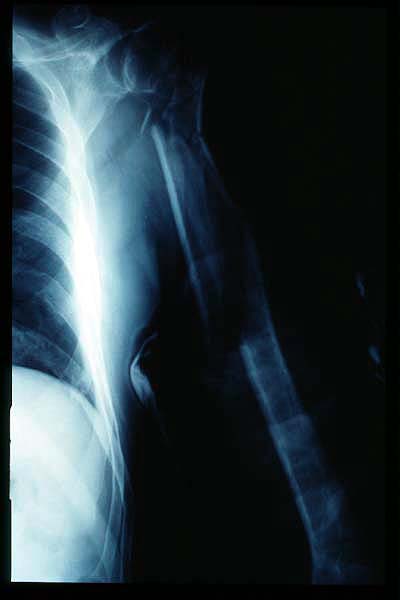

Fractura impactada de húmero .

Fractura de húmero, intensa desviación de fragmentos

Fractura de húmero.

Fractura compleja de húmero.

Fractura de diáfisis de húmero.